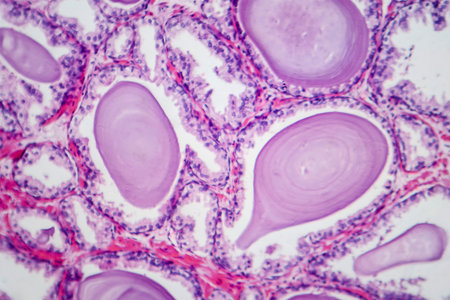

Light micrograph of teratoma, a tumor made up of several different types of tissue, such as hair, teeth, muscle, or bone. Teratoma is typically found in the ovary, testicle, or coccyx